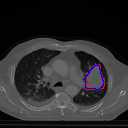

Figure 5 shows a comparison between predictions by the MultiResUNet model and Deeply supervised MultiResUNet model. It can be seen that the latter can delineate the tumor edges more accurately than the former. The ground truth (shown in red) and the prediction (shown in blue) have a more consistent alignment with each other in Deeply Supervised MultiResUNet’s prediction.